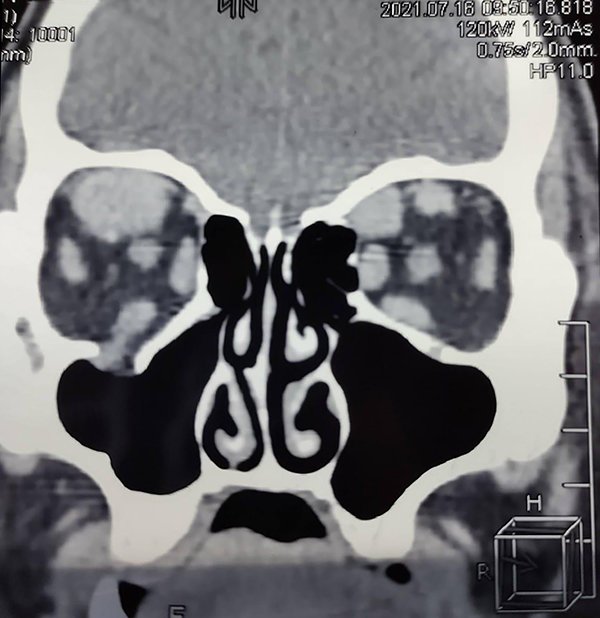

La TAC de órbita con cortes coronal y axial mostraba una masa a nivel del recto superior y oblicuo mayor derechos intraconal (figs. 6 y 7).

Figura 6. TC de órbita, corte coronal: engrosamiento de los músculos recto superior y oblicuo mayor derechos.